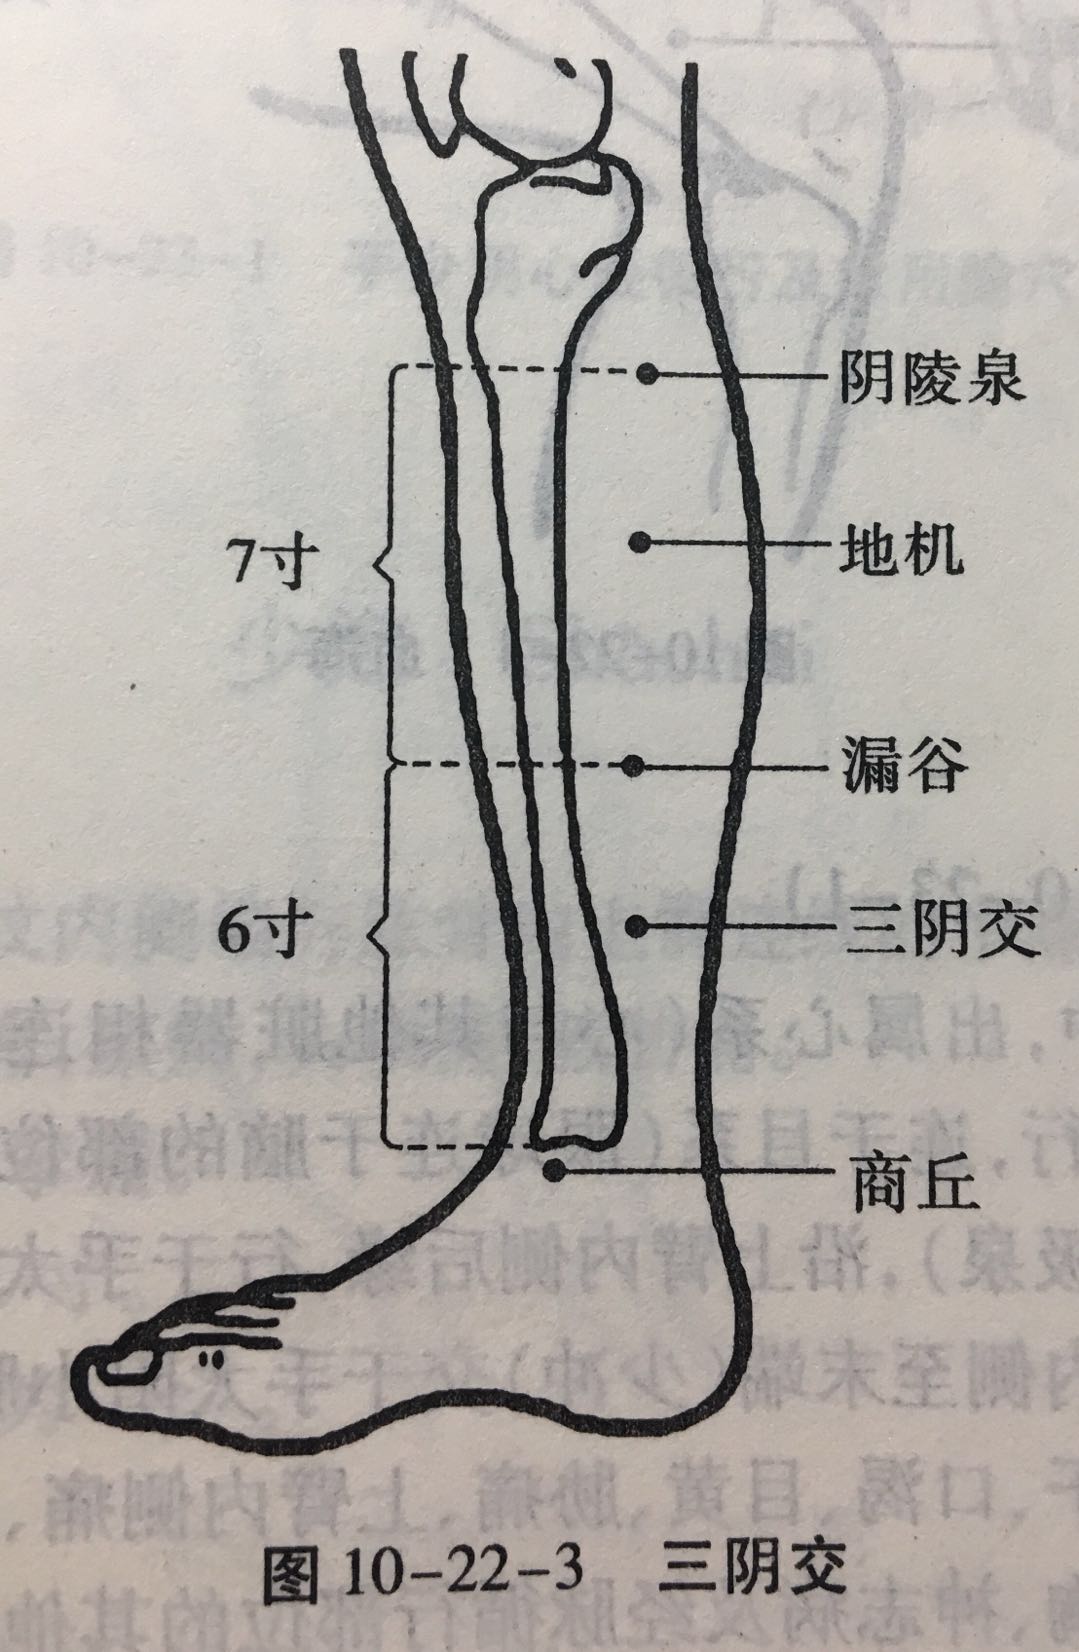

三阴交

【定位】 在小腿内侧,当足内踝尖上 3 寸,胫骨内侧缘后方(图 10-22-3)。

【主治】 肠鸣腹胀,泄泻,月经不调,带下,阴挺,不孕,滞产,遗精,阳痿,遗尿,疝气,失眠,下肢痿痹,脚气。

【配伍】 配足三里治肠鸣泄泻,配中极治月经不调,配子宫治疗阴挺,配大敦治疝气,配内关、神门治失眠。

【刺灸法】 直刺 1 ~ 1.5 寸。

【附注】 (1)足太阴、少阴、厥阴经交会穴。(2)孕妇禁针。

阴陵泉

【定位】 在小腿内侧,当胫骨内侧髁(kē)后下方凹陷处。

【主治】 腹胀,泄泻,水肿,黄疸,小便不利或失禁,膝痛。

【配伍】 配肝俞、至阳治黄疸,阴陵泉透阳陵泉治膝痛。

【刺灸法】 直刺 1 ~ 2 寸。

【附注】 足太阴经所入为“合”。